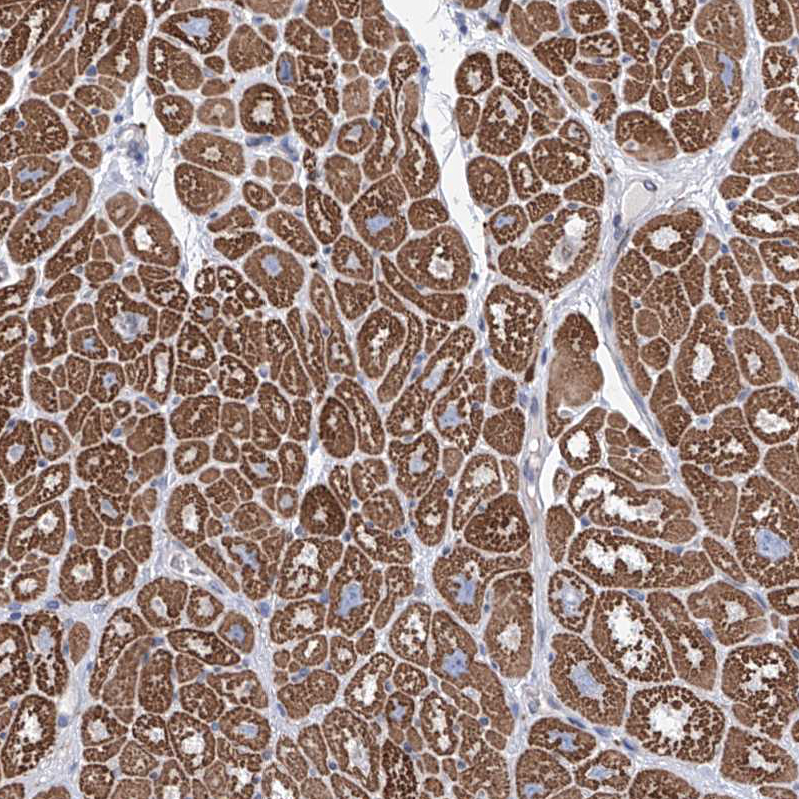

Immunohistochemical staining of human heart muscle shows strong cytoplasmic positivity in cardiomyocytes.